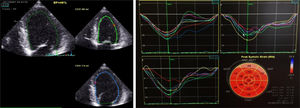

Uma semana após a alta programou‐se a realização de um terceiro ETT, demonstrando uma função sistólica global do VE conservada (FEj 52%) com strain global longitudinal normal (‐20,2%) (Figure 4). A oito meses de follow‐up sem novos internamentos, sem queixas do foro cardiovascular.